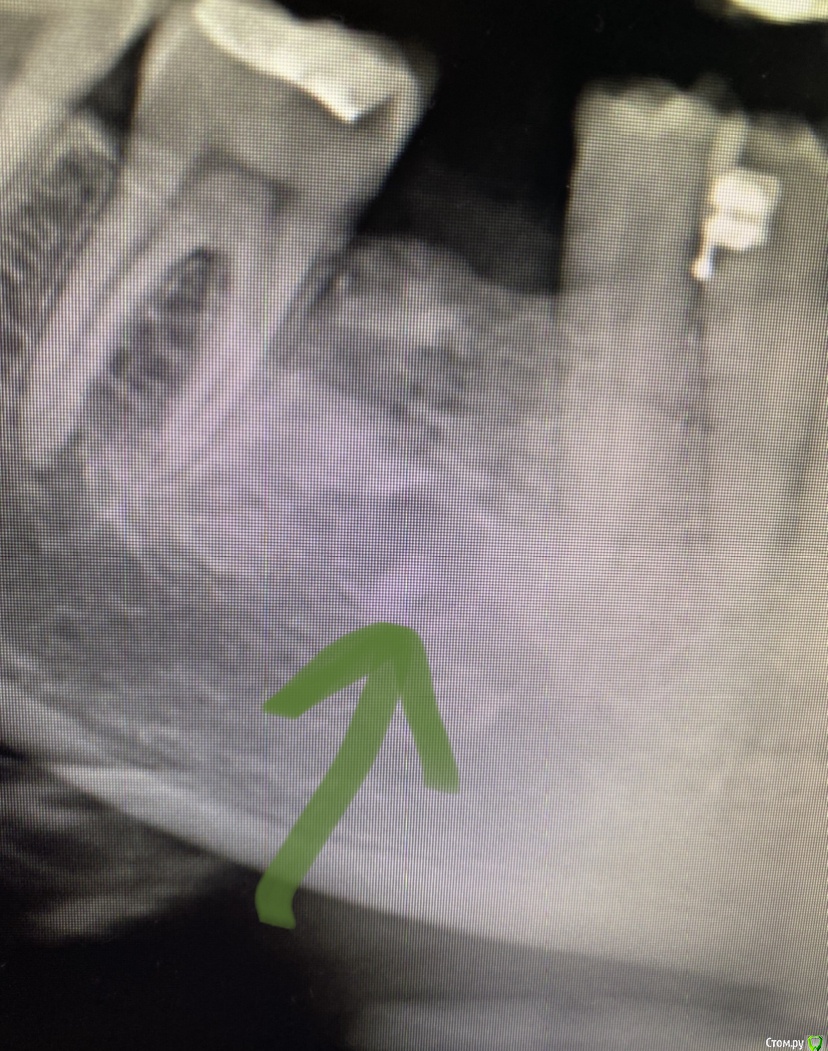

It'sGeorgy Опубликовано 7 февраля, 2020 Автор Поделиться Опубликовано 7 февраля, 2020 (изменено) Заколхозил лоскут => налепил житкотекучего на кость(стрелкой на снимке), чтобы понять там ли планирую пилить, сделал оптг => выпилил => вытащил => через месяц пластика мягких тканей + имплантат. А ментальное отверстие в 2 мм от окна отлично держало меня в тонусе на протяжении все операции. Изменено 7 февраля, 2020 пользователем It'sGeorgy 1 Ссылка на комментарий